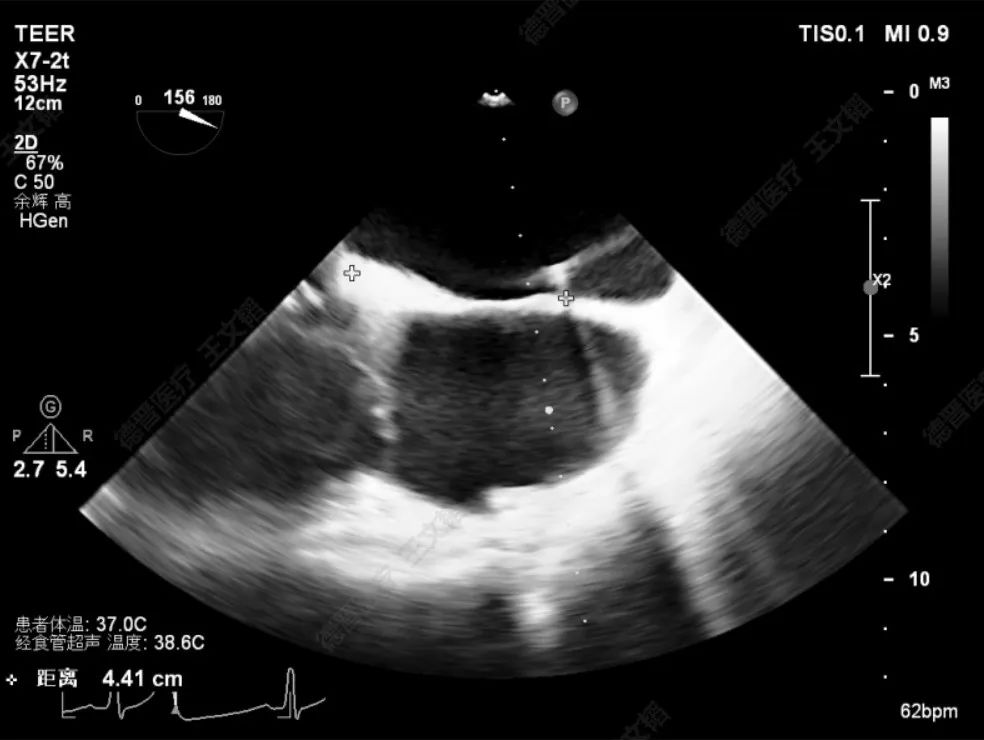

患者为73岁老年男性,经食道超声检查提示:急性二尖瓣腱索断裂合并反流,前叶长度:2.8cm,后叶长度:1.7cm,脱垂宽度:18mm,脱垂高度:8mm,瓣口面积:6.5cm²。

术前影像

左房极小

房间隔增厚

房间隔穿刺高度